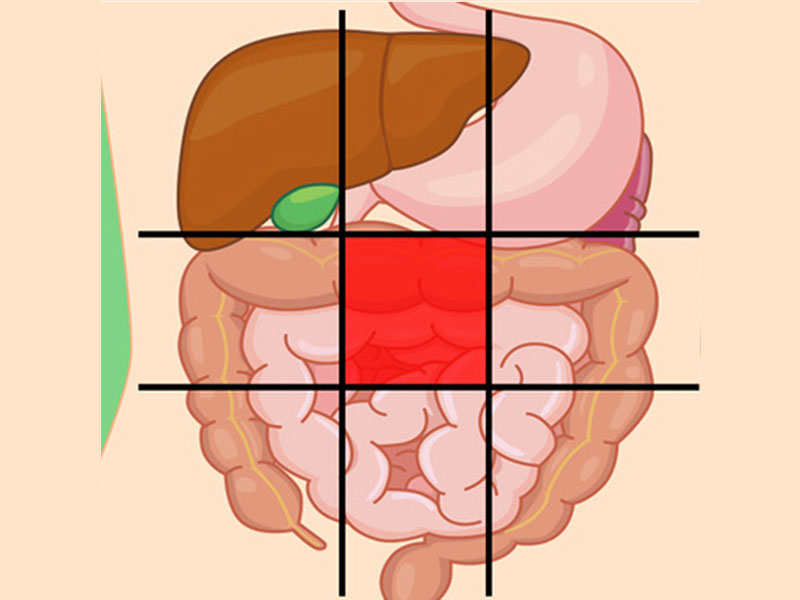

درد مرکز شکم نشانه چیست؟

احساس ناراحتی در این بخش از شکم معمولاً با مشکلات در رودهها همراه است.

دلایل ناراحتی در این ناحیه شامل موارد زیر میباشد:

- آپاندیس

- گاستروانتریت (بیماری التهاب معده)

- التهاب روده

- انسداد روده

- جراحت

- اوره (جمع شدن مواد زائد در خون شما)

درد شکم سمت چپ پایین نشانه چیست؟

این بخش شامل روده بزرگ است، پس اگر مشکلی برای این اندام پیش بیاید، در این بخش احساس درد میکنید.

علل شایع درد این ناحیه عبارتاند از:

- بیماری کرون

- سندرم روده تحریکپذیر

- سرطان

- عفونت کلیه

- کیستهای تخمدان

- آپاندیس

درد شکم سمت راست پایین نشانه چیست؟

این ناحیه از شکم آپاندیس را شامل میشود و درد آن ممکن است به دلیل مشکلات آپاندیس باشد.

علل رایج درد این بخش:

- آپاندیس

- فتق (هنگامیکه یک ارگان از طریق یک نقطهضعف در عضلات شکم بیرون میزند و برآمده میشود)

- عفونت کلیه

- سرطان

- آنفولانزا